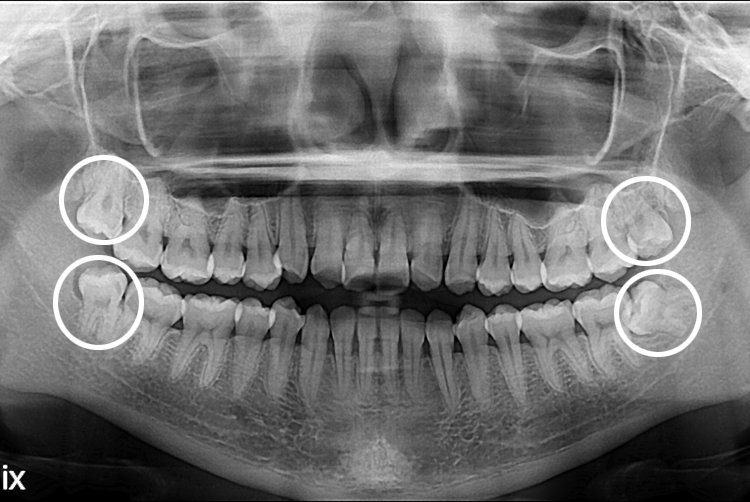

[사랑니] 단순매복 + 복잡매복 + 완전매복 사랑니 발치

치료후 : 2017-11-22

세종치과는 구강악안면외과학 박사이신 원장님이 발치하는 치과 입니다.